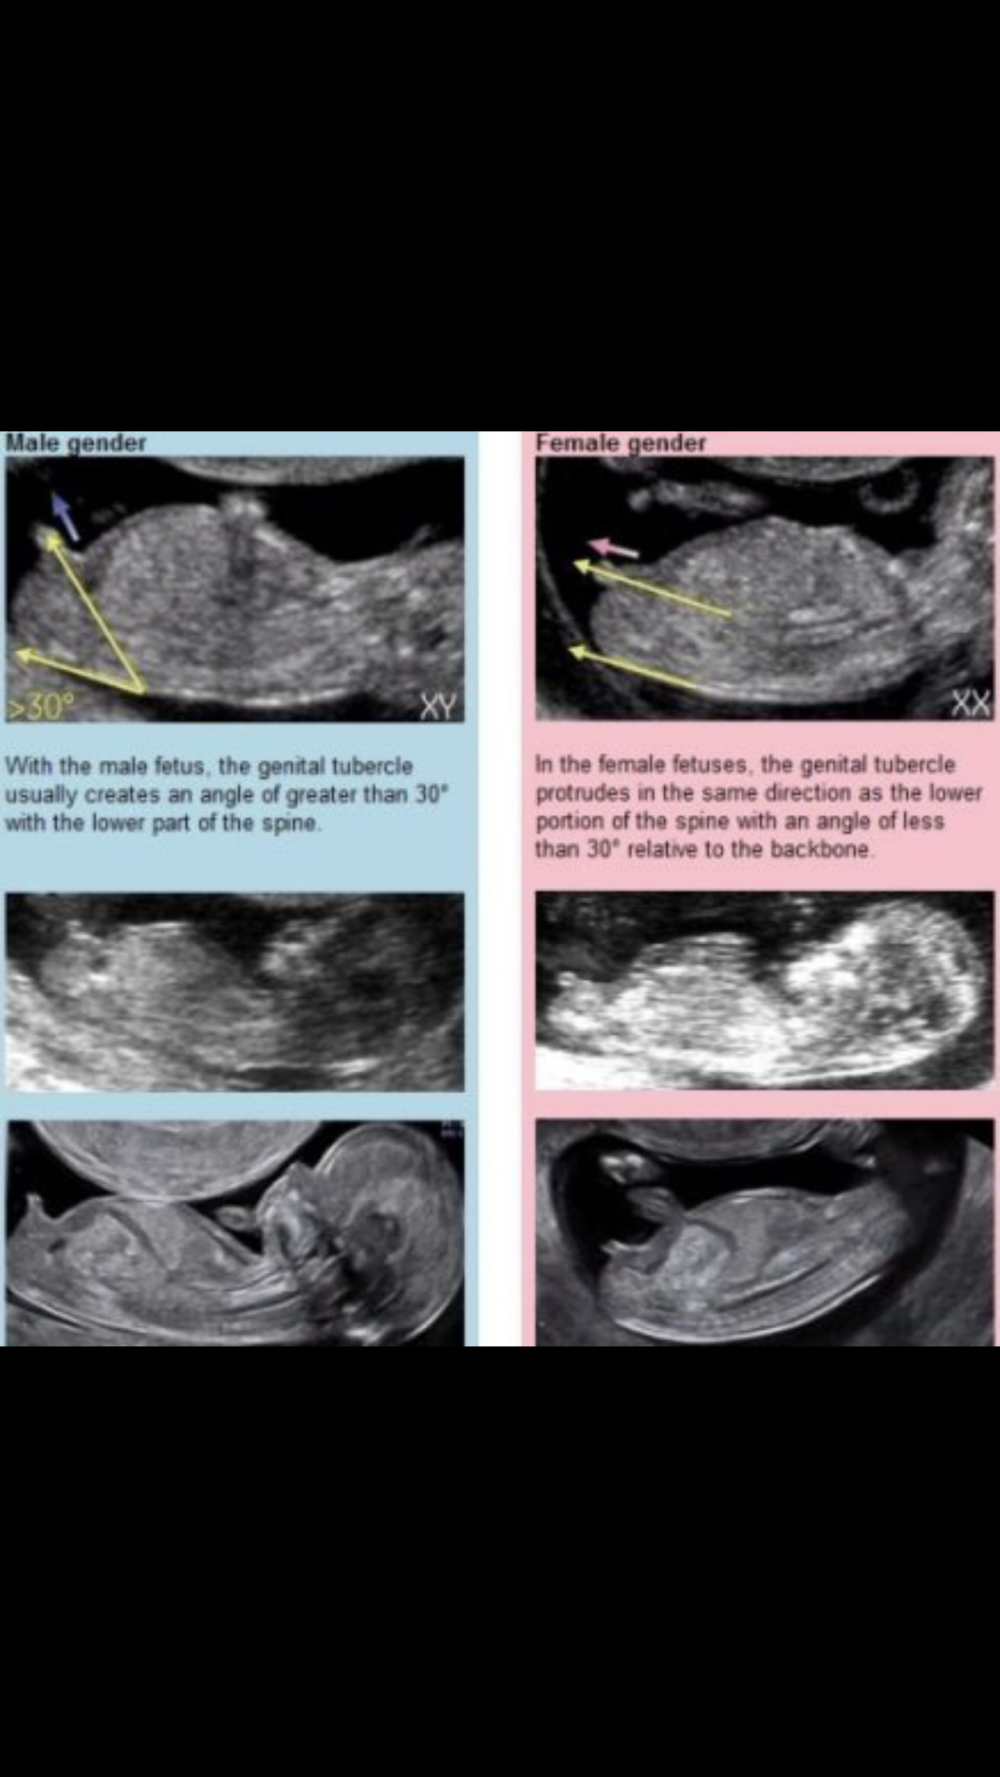

شوفو الصوره انا سوناري مو كذا

مالقيت البروز